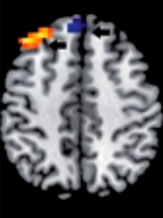

Esta “teoría dual del razonamiento” ha recibido recientemente un sólido sustento biológico a través de estudios con imágenes neurofuncionales del cerebro, que han demostrado dos patrones anatómicos diferentes de activación de áreas corticales durante los procesos de pensamiento no analítico y analítico involucrados en la toma de decisiones médicas.

Pensamiento analítico

Pensamiento no analítico

Durning SJ, Costanzo ME, Van Der Vleuten C. Functional neuroimaging correlates of thinking flexibility and knowledge structure in memory: Exploring the relationships between clinical reasoning and diagnostic thinking. Med Teach. 2015 Jun 16:1-8